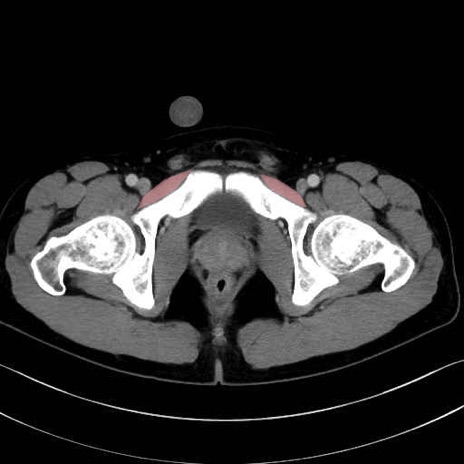

恥骨筋 (Pectineus)

長内転筋 (Adductor longus)